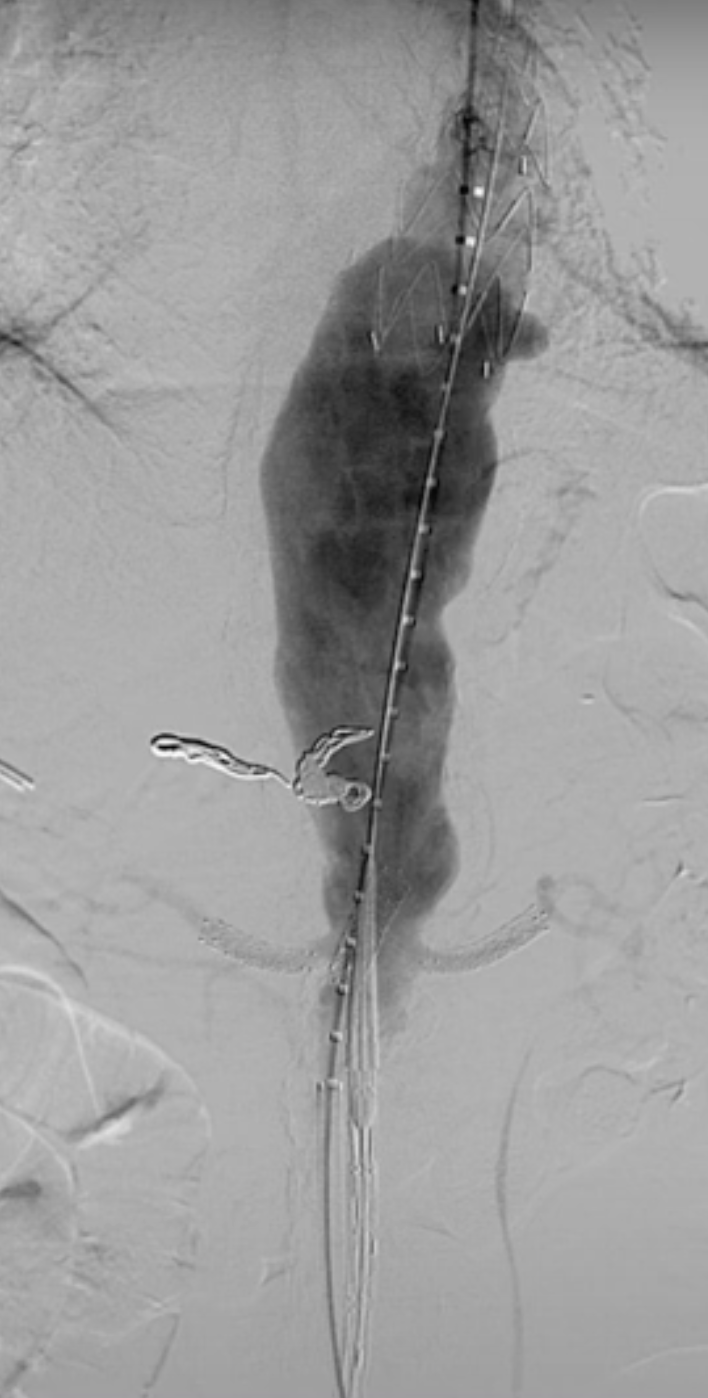

在植入主动脉支架后,首先开通SMA,配合可调弯导管调整激光导管角度,多角度视图下确保对准。发射激光(60-60mJ/mm2),激光穿透主体支架覆膜后立即推进导丝。

确认导丝进入靶血管后移除激光导管,依次使用4mm快交球囊、5mm切割球囊进行扩张开窗,交换入35系统导丝,在预植入的支架内引入VBX球扩覆膜支架,远端超过预植入支架远端,近端伸入主动脉3-5毫米,扩张球囊使VBX释放。

再次扩张VBX支架近端使其锚定于主动脉支架上。

造影确认开窗支架的通畅性。

在其他目标动脉内重复以上操作。

在激光开窗前多角度确认。